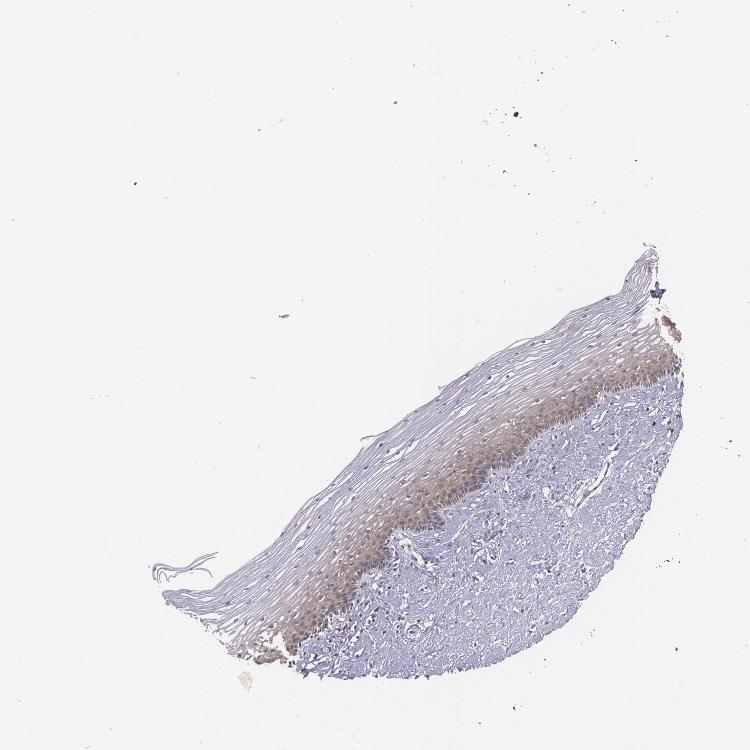

CERVIX - Antibody stainingi

Antibody staining in the annotated cell types in the current human tissue is reported as not detected, low, medium, or high, based on conventional immunohistochemistry profiling in selected tissues. This score is based on the combination of the staining intensity and fraction of stained cells.

Each image is clickable and will lead to virtual microscopy that enables deeper exploration of all samples and also displays staining intensity scores, fraction scores and subcellular localization as well as patient and tissue information for each sample.

Antibody HPA001535

Glandular cells High

Squamous epithelial cells Medium